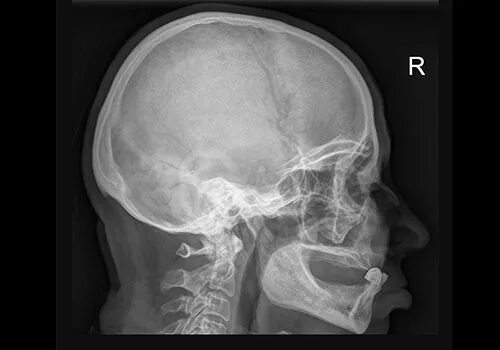

Остеопатия череп